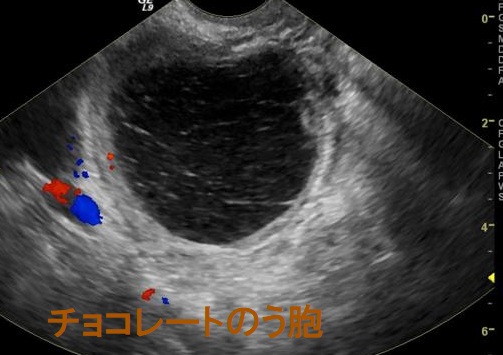

チョコレートのう胞(卵巣子宮内膜症、ovarian chocolate cyst)は、子宮内膜が本来存在しないはずの卵巣に発生する子宮内膜症の一種です。 20~30代前半に好発し、生理周期に合わせて子宮内膜が剥離し出血をおこします。それが卵巣内にチョコレートの様な状態で蓄積し、チョコレートのう胞(チョコレート嚢胞)を形成します。

甲状腺乳頭癌の術後にDWIBS:ドゥイブス を行った際、偶然発見されたチョコレートのう胞(卵巣子宮内膜症)、

チョコレートのう胞(卵巣子宮内膜症)は、0.7-1.6%が子宮内膜症関連卵巣癌(EAOC)に悪性転換します(Reproduction. 2004 Mar; 127(3):293-304.)。組織型は明細胞癌、類内膜癌など。チョコレートのう胞(卵巣子宮内膜症)の既往がある女性において、衣服がきつくなるなど腹部膨満感・下腹部膨隆の自覚症状がおこり、下腹部に可動性のない腫瘤を触れた場合、子宮内膜症関連卵巣癌(EAOC)が疑われます。